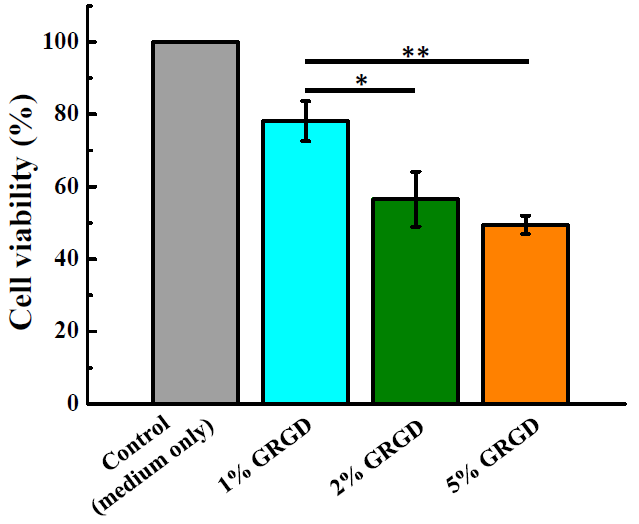

2.3. Cell Culture and MTT Assay

3.2. Biocompatibility in Different Concentrations of the GRGD Peptide